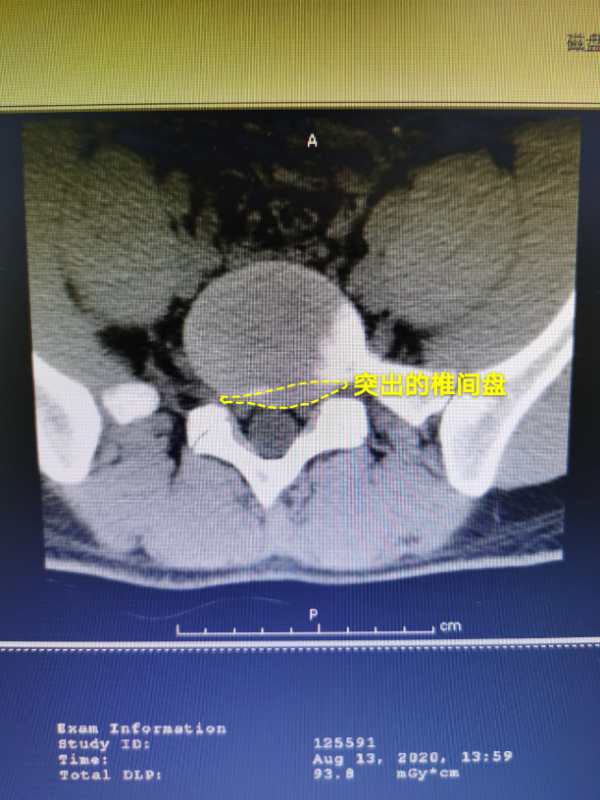

8月的一天,塞德里克因腰痛、行走困難,慕名來到哈爾濱市第一醫院求醫。五個月前,他在無明顯誘因的情況下出現左下肢疼痛,從左側臀部、大腿後方放散至小腿前外側、小腿後方、足背外側及足底,並伴有麻木,經臥床、口服非甾體類抗炎藥後症狀雖有好轉,但一個月前腰腿疼痛再次發作,逐步加劇,出現躺在床上左腿不能抬高、下地行走困難等情況。經再次保守治療無效,疼痛經常會讓他在夜晚輾轉反側,徹夜難眠,嚴重影響了塞德里克的情緒和生活質量。在哈爾濱市第一醫院門診行MRI檢查後提示:L5/S1(腰5、骶1)腰椎間盤突出,入住骨外一科。

骨外一科盧微主任帶領李心龍副主任、接診醫生副主任醫師張雲奇、副主任醫師於德軍、住院醫師曲廣東對病人進行了細緻的查體、評估並完善了相關檢查。塞德里克L5/S1(腰5、骶1)雖然只是一個節段的椎間盤突出,卻導致了兩個神經根受壓,並且伴有椎間孔狹窄及第五腰椎橫突肥大,這種情況在臨床工作中並不多見。盧微主任立即組織全科醫生召開術前討論會,制定科學合理的微創手術方案及術後康復計劃並組建微創手術小組,擇日為塞德里克應用椎間孔鏡實施脊柱微創手術。